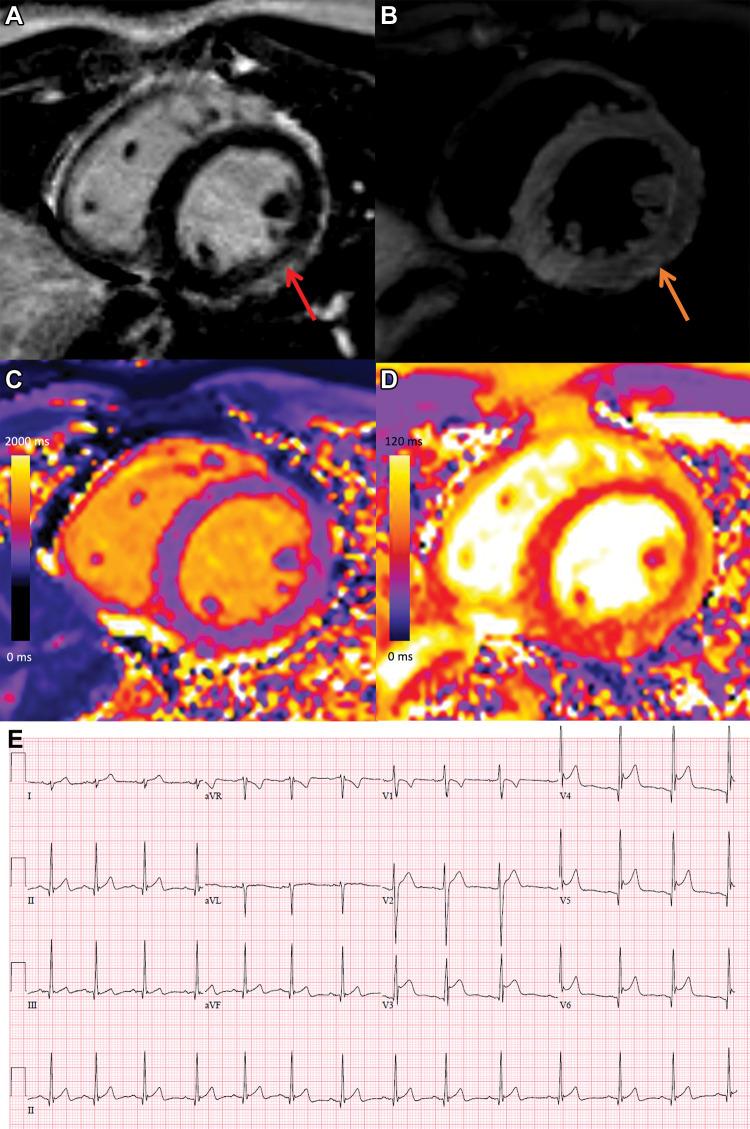

Myocardial Injury Pattern at MRI in COVID-19 Vaccine-Associated Myocarditis.

Background There are limited data on the pattern and severity of myocardial injury in patients with COVID-19 vaccination-associated myocarditis. Purpose To describe myocardial injury following COVID-19 vaccination and to compare these findings to other causes of myocarditis. Materials and Methods In this retrospective cohort study, consecutive adult patients with myocarditis with at least one T1-based and at least one T2-based abnormality at cardiac MRI performed at a tertiary referral hospital from December 2019 to November 2021 were included. Patients were classified into one of three groups: myocarditis following COVID-19 vaccination, myocarditis following COVID-19 illness, and other myocarditis not associated with COVID-19 vaccination or illness. Results Of the 92 included patients, 21 (23%) had myocarditis following COVID-19 vaccination (mean age, 31 years ± 14 [SD]; 17 men; messenger RNA-1273 in 12 [57%] and BNT162b2 in nine [43%]). Ten of 92 (11%) patients had myocarditis following COVID-19 illness (mean age, 51 years ± 14; three men) and 61 of 92 (66%) patients had other myocarditis (mean age, 44 years ± 18; 36 men). MRI findings in the 21 patients with vaccine-associated myocarditis included late gadolinium enhancement (LGE) in 17 patients (81%) and left ventricular dysfunction in six (29%). Compared with other causes of myocarditis, patients with vaccine-associated myocarditis had a higher left ventricular ejection fraction and less extensive LGE, even after controlling for age, sex, and time from symptom onset to MRI. The most frequent location of LGE in all groups was subepicardial at the basal inferolateral wall, although septal involvement was less common in vaccine-associated myocarditis. At short-term follow-up (median, 22 days [IQR, 7-48 days]), all patients with vaccine-associated myocarditis were asymptomatic with no adverse events. Conclusion Cardiac MRI demonstrated a similar pattern of myocardial injury in vaccine-associated myocarditis compared with other causes, although abnormalities were less severe, with less frequent septal involvement and no adverse events over the short-term follow-up. © RSNA, 2022 See also the editorial by Raman and Neubauer in this issue.